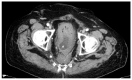

Neoadjuvant radiochemotherapy (RCT) and lately total neoadjuvant therapy (TNT) improved local recurrence rates of rectal cancer significantly compared to total mesorectal excision (TME) alone. Yet the occurrence and impact of late local recurrences after many years appears to be a distinct biological problem. We included n = 188 patients with rectal cancer after RCT and radical resection in this study; n = 38 of which had recurrent disease (sites: local (8.0%), liver (6.4%), lung (3.7%)). We found that 68% of all recurrences developed within the first two years. Four patients, however, experience recurrence >8 years after surgery. Here, we report and characterize four cases of late local recurrence (10% of patients with recurrent disease), suggesting that neoadjuvant therapy in principle delays local recurrence.